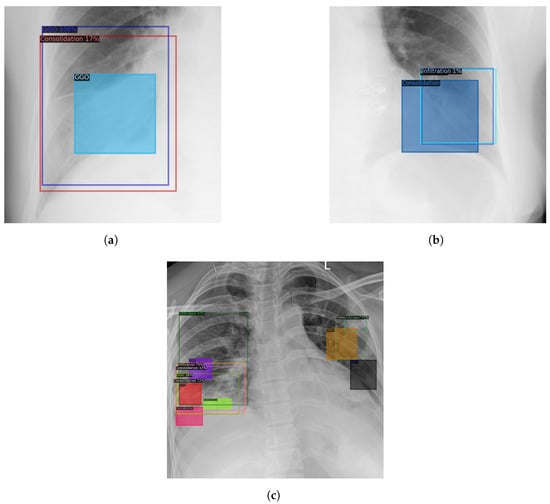

5.3. The Bias of Annotating Style